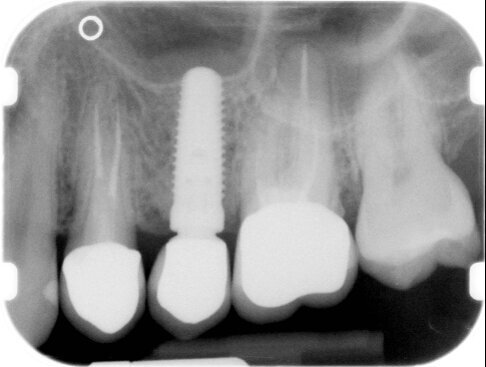

Avvenuta la fissazione degli elementi (Fig. 16), procediamo al controllo radiografico sempre con il centratore e laddove possibile si utilizza un gig in silicone che potrà riprodurre sempre la medesima sequenza proiettiva radiografica. Si possono comparare le immagini radiografiche iniziali e finali vedendo come all’apice del dente naturale sia modellato il confine con la parete del seno mascellare superiore (Fig. 2) con il rimodellamento che la stessa compie attorno all’impianto ad un anno dal carico (Fig. 17).

Fig. 2 - Radiografia endorale di controllo, eseguita con centratore.

Fig. 17 - Radiografia di controllo a 1 anno dal carico.